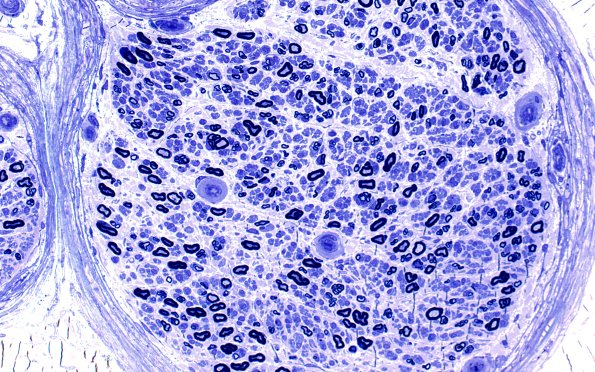

Washington University Experience | PERIPHERAL NEUROPATHY | 11 VASCULITIS - VASCULOPATHY | 2 Vasculopathy | 15A2 (Case 15) HIEM Plastic 20X

15A2,3 Some endoneurial blood vessels show mild to-moderate mural thickening at different magnifications. (plastic sections)